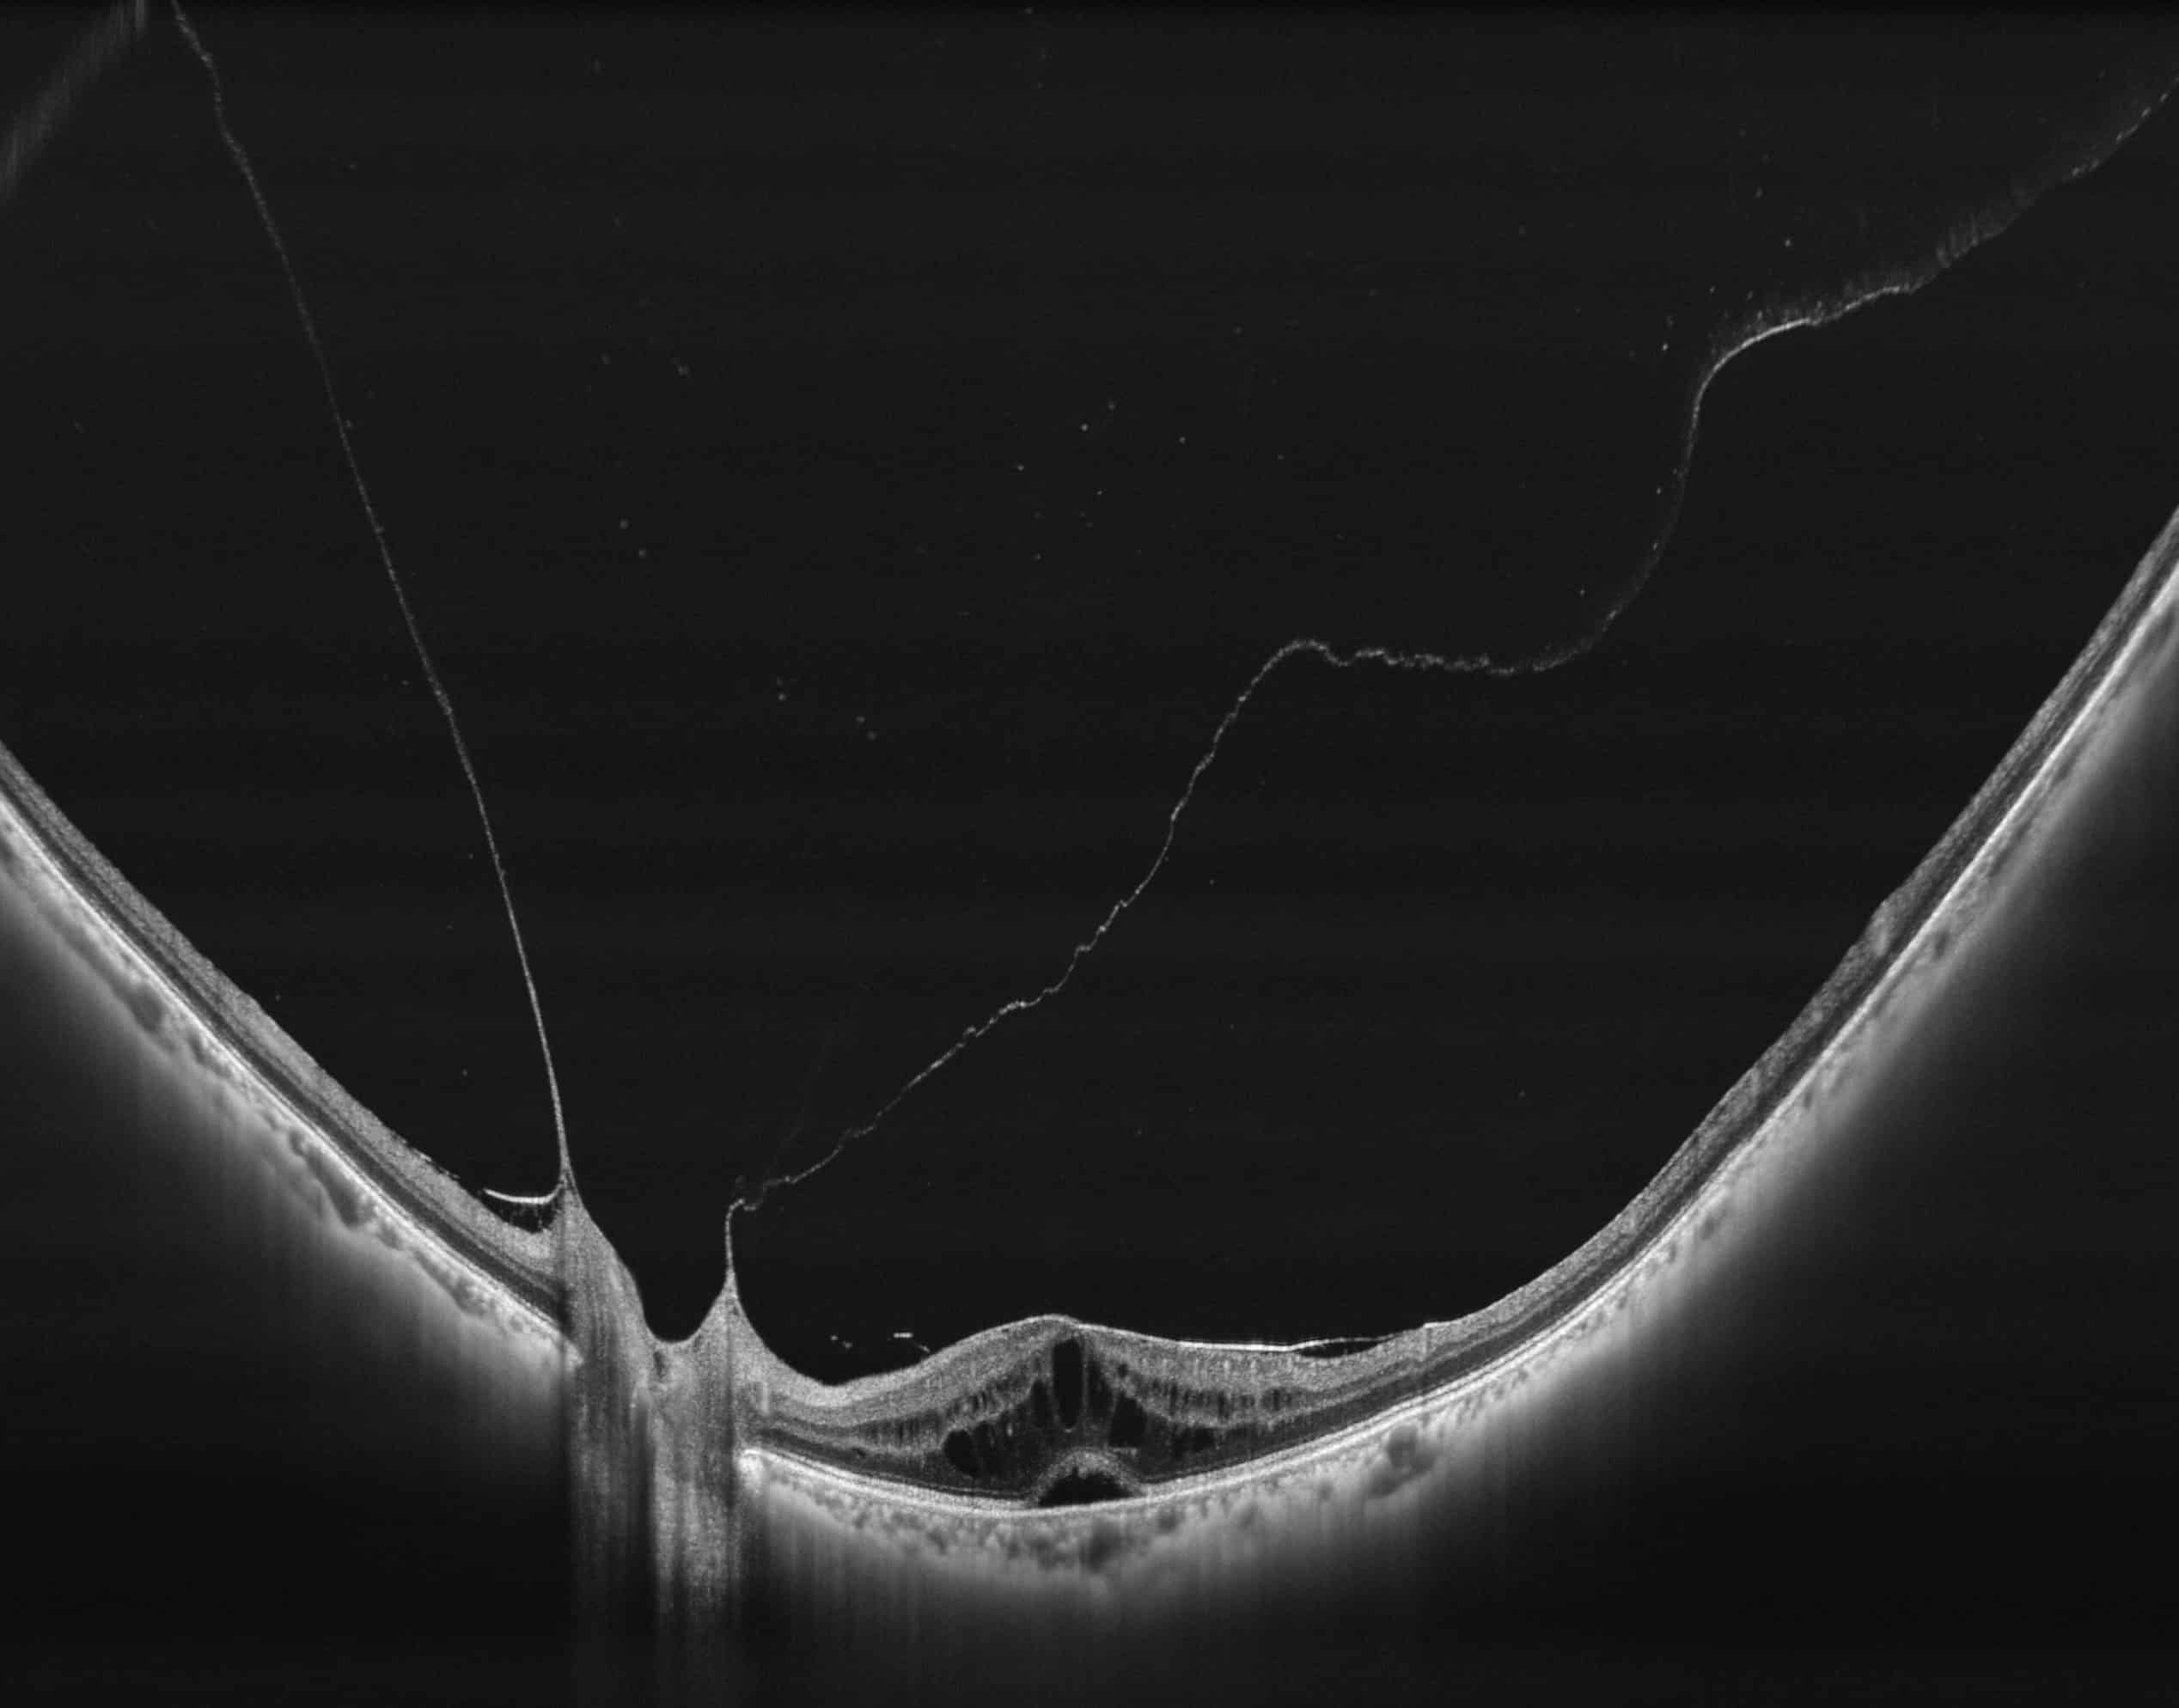

400kHz speed full-range swept-source OCT for anterior and posterior

- Full-Range wide-field Swept Source OCT

- HD Anterior Scan with Anterior OCTA